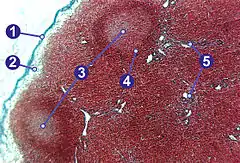

A lymph node is divided into compartments called nodules (or lobules), each consisting of a region of cortex with combined follicle B cells, a paracortex of T cells, and a part of the nodule in the medulla.[15] The substance of a lymph node is divided into the outer cortex and the inner medulla.[3] The cortex of a lymph node is the outer portion of the node, underneath the capsule and the subcapsular sinus.[15] It has an outer part and a deeper part known as the paracortex.[15] The outer cortex consists of groups of mainly inactivated B cells called follicles.[4] When activated, these may develop into what is called a germinal centre.[4] The deeper paracortex mainly consists of the T cells.[4] Here the T-cells mainly interact with dendritic cells, and the reticular network is dense.[16]

The medulla contains large blood vessels, sinuses and medullary cords that contain antibody-secreting plasma cells. There are fewer cells in the medulla.[4]

The medullary cords are cords of lymphatic tissue, and include plasma cells, macrophages, and B cells.

Cells

In the lymphatic system a lymph node is a secondary lymphoid organ.[4] Lymph nodes contain lymphocytes, a type of white blood cell, and are primarily made up of B cells and T cells.[4] B cells are mainly found in the outer cortex where they are clustered together as follicular B cells in lymphoid follicles, and T cells and dendritic cells are mainly found in the paracortex.[17]

There are fewer cells in the medulla than the cortex.[4] The medulla contains plasma cells, as well as macrophages which are present within the medullary sinuses.[17]

As part of the reticular network, there are follicular dendritic cells in the B cell follicle and fibroblastic reticular cells in the T cell cortex. The reticular network provides structural support and a surface for adhesion of the dendritic cells, macrophages and lymphocytes. It also allows exchange of material with blood through the high endothelial venules and provides the growth and regulatory factors necessary for activation and maturation of immune cells.[18]